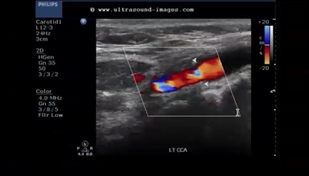

Patient presents with recent history of syncope. New onset of HTN and HX of smoking 1 pack per day (ppd) x 25 years.

Carotid ultrasound exam ordered. Considering following questions and please answer.

1. In patient presentation, which item is the symptom for carotid ultrasound exam?

2. In patient presentation, identify the risk factors for atherosclerosis and carotid artery disease.

3. Consider image, which vessel contain some blue colors?

4. Is the 'blue' pathological?

5. What is the color blue representing?

Syncope

HTN and smoking

Prox ICA (bulb)

no

eddie currents from flow reversal in bulb